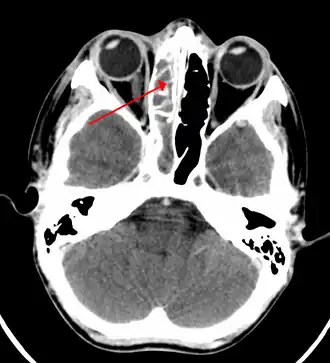

TAC de sinusite na extremidade do seio etimóide

Tomografia demonstrando sinusite maxilar à direita